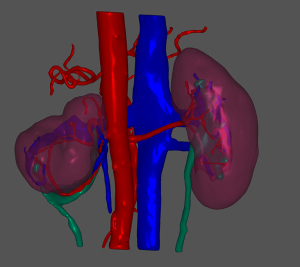

A 45-year-old woman was admitted to hospital complaining of a 1-month history of dizziness, and a transient ischemic attack was diagnosed. During a lung examination, her left kidney was found to be abnormal. The patient was not known to have kidney abnormalities, and there was no genetic history of this condition in her family. The patient did not present clinical symptoms of low back pain, hematuria, or urinary tract infection, and laboratory tests of renal function and urine routine were within normal ranges. The patient had no history of hypertension. A CT plain scan showed abnormalities in the left renal artery, vein, and ureter, and a reversed renal parenchyma with the collecting system protruding, while the right kidney was completely normal. Enhanced CT suggested that there was an artery in the left kidney, which entered the renal parenchyma in a mesh shape. There were 2 primary thick branches of deep veins, which merged with the reproductive vein at the renal pedicle and then merged into the inferior vena cava. The renal parenchyma was in a state of eversion and folding, and the renal papilla was prominent. Each renal papilla corresponded to a renal calyx, which converged into the renal pelvis on the ventral side (Figures 1,2). Using a software application (Mimics Innovation Suite 19.0, Materialise, Leuven, Belgium), we created a 3D reconstruction of the patient’s kidneys. The 3D-reconstructed images (Figures 3,4) showed that the right kidney was normal in anatomy and that the left kidney was abnormal. In Figures 3,4, it can be seen more intuitively and clearly that the left kidney has poor rotation, irregular physical contours, and an uneven surface; the renal pelvis and ureter are distributed in a “Y” shape. The final clinical diagnosis was CAKUT, and the patient’s clinical symptoms disappeared after conservative treatment. As the patient had no urinary system discomfort and her physical and laboratory examinations were normal, we prescribed a dynamic observation treatment plan with annual renal function and urinary system USs.

In this case, we only performed a 3D reconstruction based on a plain scan with enhanced imaging. We did not create an actual 3D print due to cost. However, through 3D image reconstruction, we used computer software to provide a 3D explanation to the patient, which assuaged their concerns and doubts and helped develop an active monitoring treatment plan. The patient said that the 3D reconstruction technology allowed her to understand the kidney problems more intuitively and dispelled her worries about the disease.